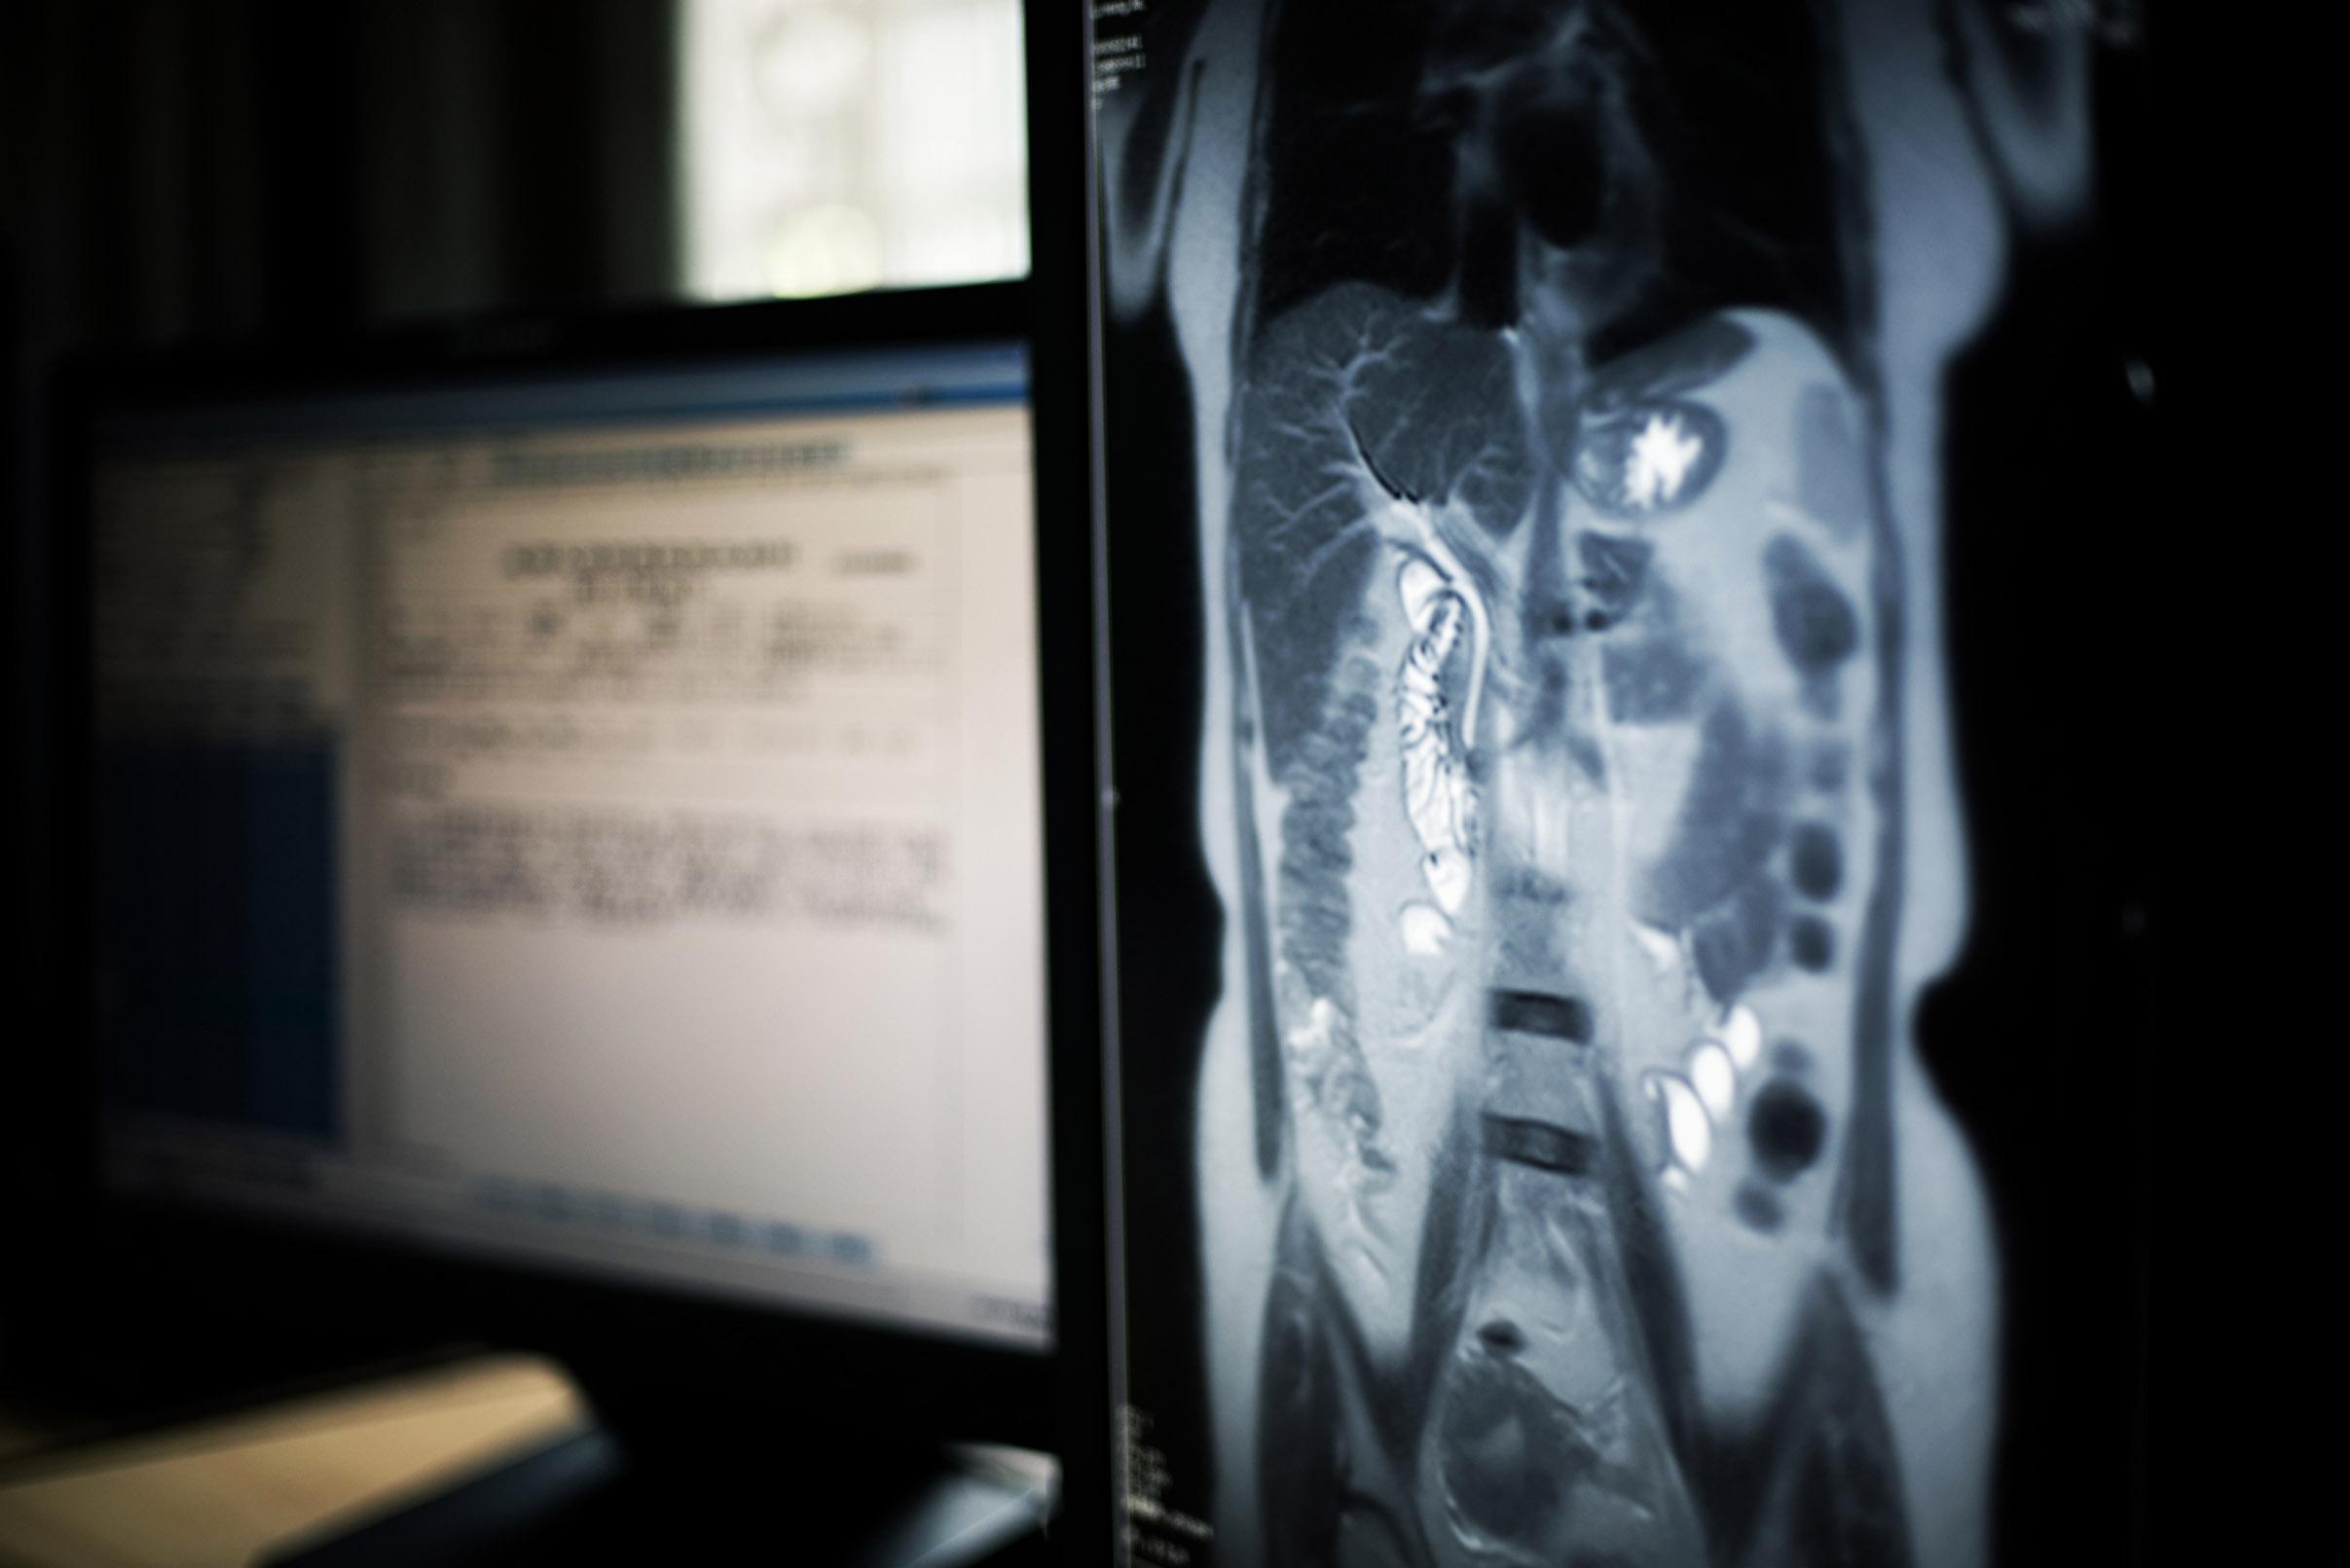

- Scanner et échographie abdominale : ces examens permettent de visualiser le foie et le pancréas.

- IRM : elle peut être nécessaire pour affiner l’exploration du foie notamment.